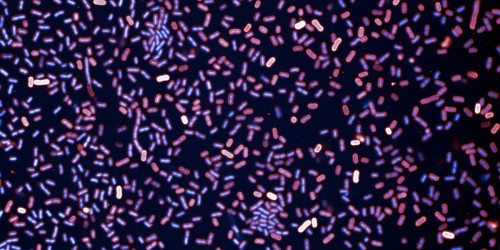

Caroline Zellmer’s research focuses on understanding drug-resistant bacteria to develop alternatives to antibiotics.